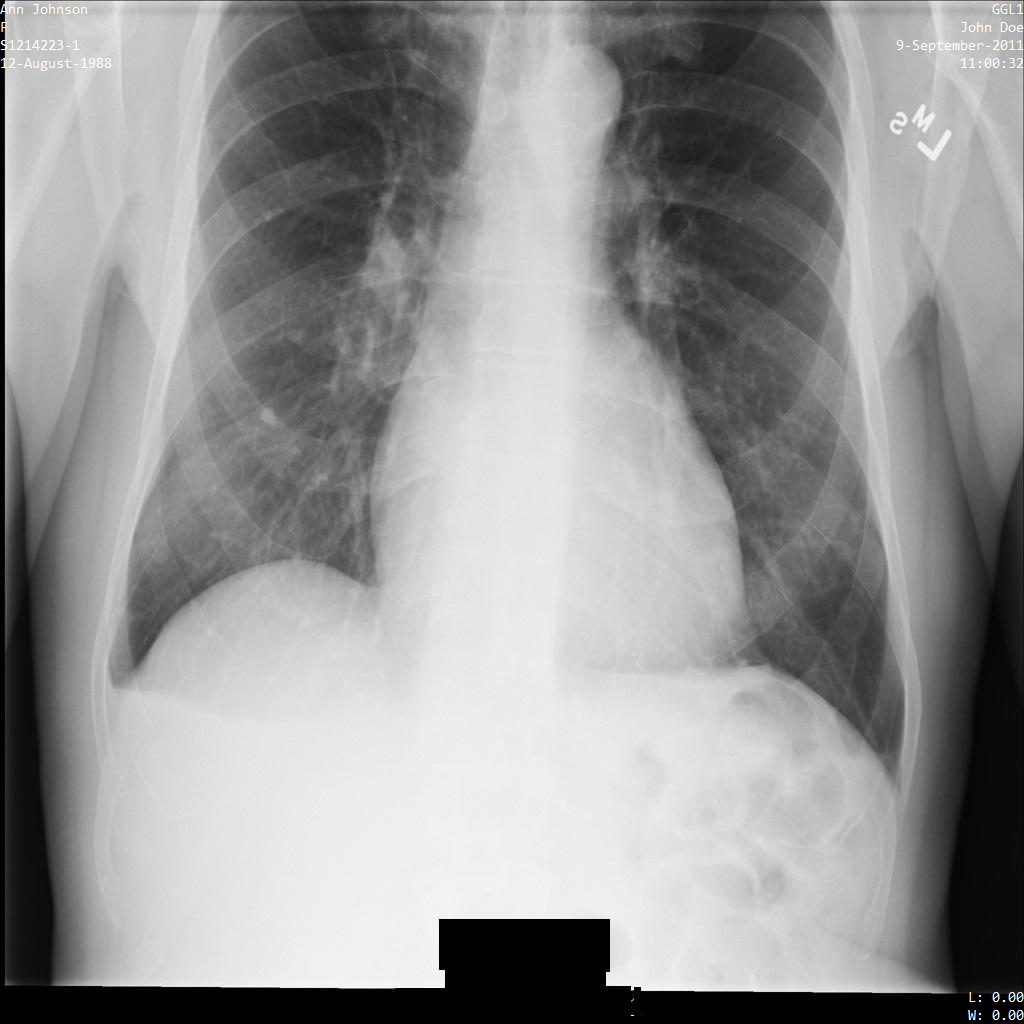

En cada una de las siguientes secciones, se proporcionan ejemplos de cómo desidentificar datos de DICOM mediante varios métodos. Se proporciona un resultado de la imagen desidentificada en cada muestra. En cada muestra, se usa la siguiente imagen original como su entrada:

Puedes comparar la imagen de salida de cada operación de desidentificación con esta imagen original para ver los efectos de la operación.

Después de enviar la imagen a la API de Cloud Healthcare, la imagen aparece de la siguiente manera. Mientras se ocultan los metadatos que se muestran en las esquinas superiores de la imagen, la información de salud protegida (PHI) quemado en la parte inferior de la imagen permanece. Para quitar también el texto quemado, consulta Oculta el texto quemado de las imágenes.